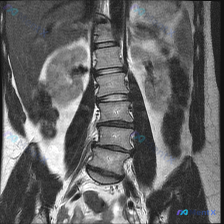

这是一张腹部MRI冠状位T2加权像,有人看了之后觉得存在脊柱侧弯,但放射科的正式报告里写的是「腰椎序列整体尚可」,还特意提了两侧腰大肌对称、双侧肾脏位置大致对称、没有明显的单侧病变导致的器官推移或结构扭曲。

实质性器官(肝、脾、肾)里也没见明确肿块、囊肿或异常高信号,腹膜后没见明显肿大淋巴结或肿块,腹腔也没游离积液。

现在的问题是:这个「看起来像侧弯」和报告里的「排列尚可」,到底该怎么看?下一步应该优先往哪个方向查?